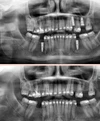

علاج الزرع السني